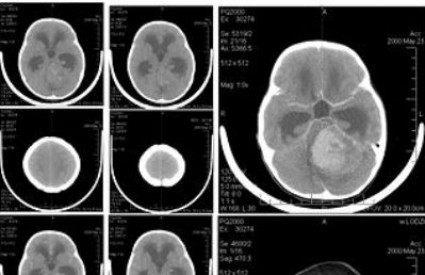

MIT#1 Ljudi koriste samo 10 posto mozga

Ovo je jedan od najnevjerojatnijih, najotpornijih i najpopularnijih mitova o mozgu i ljudskoj inteligenciji koji je, ako realno sagledate činjenično stanje, jednostavno sulud i fizički nemoguć. Prvenstveno, ako samo koristimo 10 posto mozga čemu služi ostalih 90 posto? Drugo pitanje, zašto i najmanja ozljeda mozga rezultira vegetativnim stanjem ili smrću? Doduše, postoje neki ljudi koji se ponašaju kao da imaju 10 posto mozga, no nažalost PET skenovi i magnetne rezonancije pokazuju da i oni imaju 100 postotnu aktivnost u glavi.